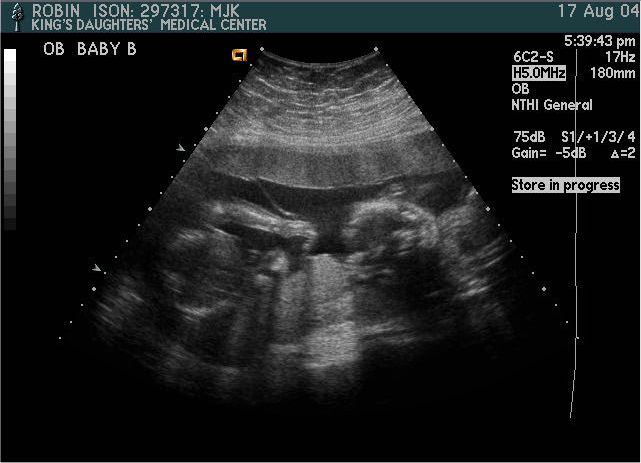

Baby B

Pictures from Ultrasound at 20 weeks.